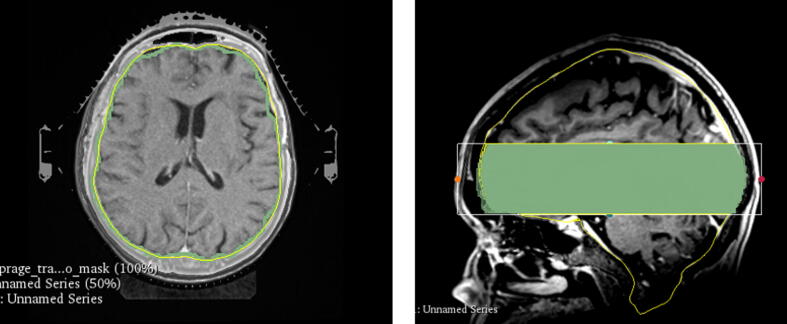

Brain contour in MRD and MRRT was defined using the open-source brain extraction tool (HD-BET, [21]), whereas the brain contour of the CT was defined using an automatic model-based segmentation tool in TPS1. The segmentations were limited to a small area that excludes the most superior and inferior areas to avoid uncertainties coming from the brain contour differences between MRI and CT that are mostly present in these areas, and enable a consistent comparison excluding regions with reduced signal in the MRI (Fig. 2). The same axial range was cropped after the registration, where the most superior area starts in the middle of the brain, and the inferior area starts before the brainstem. The tumors are not necessarily located in the limited region. Dice similarity coefficient (DSC), mean Hausdorff distance (MHD), and the 95th percentile of Hausdorff distance (HDP95) were used as evaluation metrics as recommended by the TG132 report [22]. All results for different registration metrics were evaluated using the open-source software 3Dslicer (version 4.10.2, [23]).

Figure 2.

(a) A transversal view of the segmented brain of CT (yellow) and MRI (green), and (b) a sagittal view of the cropped brain segmentation used for segmentation-based evaluation. (For interpretation of the references to colour in this figure legend, the reader is referred to the web version of this article.)